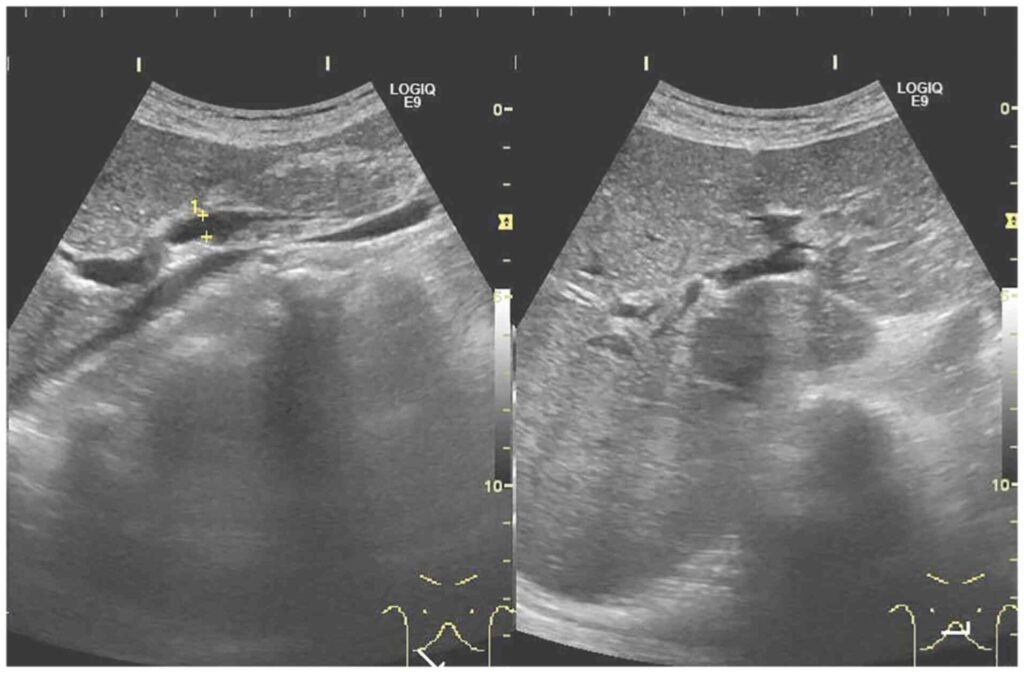

If doctors suspect ischemic hepatitis, they look for a cause. For example, they may do imaging tests to check heart function or for a blockage in the hepatic artery. These imaging tests include echocardiography, ultrasonography, magnetic resonance imaging (MRI) of blood vessels (magnetic resonance angiography), and arteriography, which involves taking x-rays after a radiopaque contrast agent (which is visible on x-rays) is injected into an artery.